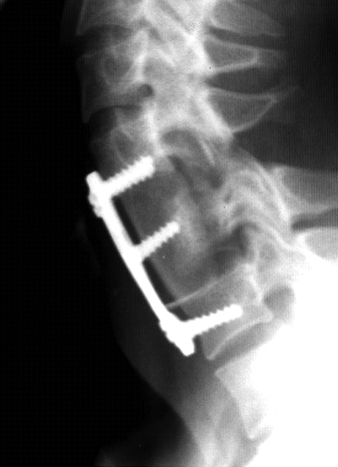

Вместо тела позвонка устанавливается шейный кейдж или сетчатый имплант (mesh) или же фрагмент подвздошной кости пациента. Далее, указанная конструкция фиксируется шейной пластиной. Т.о. спинной мозг освобождается от компрессии и создаются условия для его восстановления. (Рис.8)

Рис.8а. Схема установки сетчатого импланта MESH между телами позвонков и фиксация титановой пластиной смежных позвонков Рис.8б  Рентгенограмма шейного отдела позвоночника в боковой проекции. Титановая пластина фиксирует С4 и С6 позвонки. Средний винт фиксирует межтеловой аутотрансплантат из подвздошной кости. Рис.9. Схема ламинопластики  шейного отдела позвоночника по  типу «открытых окон» по Курокава.  Костные трансплантаты из подвздошной  кости установлены между разведенными дужками позвонков и фиксированы нитью.Стрелкой указан имплантированный трансплантат.

Рис.8б  Рентгенограмма шейного отдела позвоночника в боковой проекции. Титановая пластина фиксирует С4 и С6 позвонки. Средний винт фиксирует межтеловой аутотрансплантат из подвздошной кости.